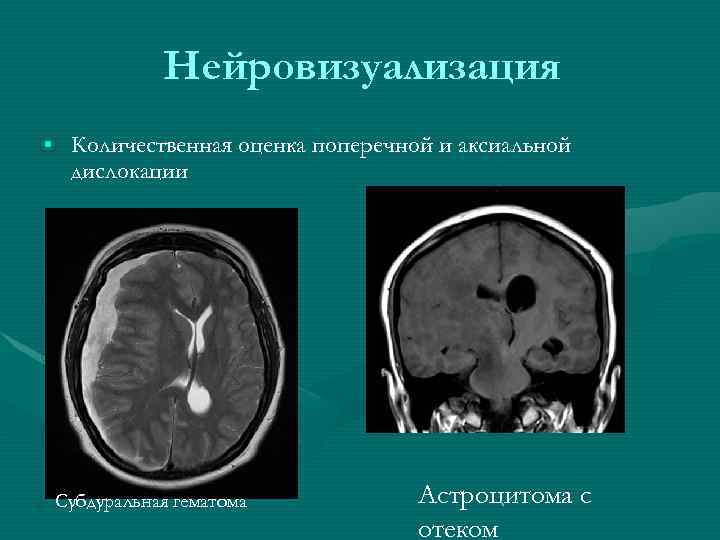

Нейровизуализация • Количественная оценка поперечной и аксиальной дислокации Субдуральная гематома Астроцитома с отеком